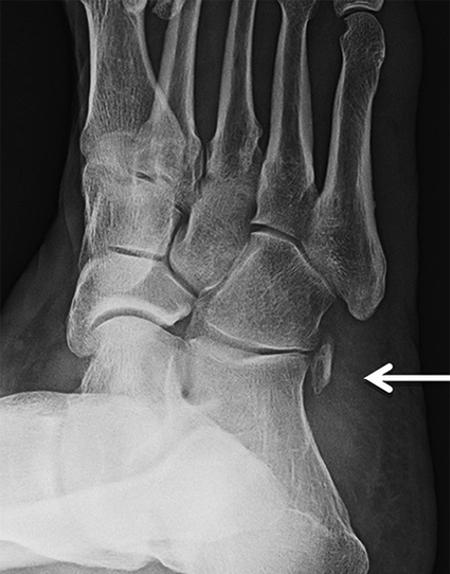

60-årig man. Röker cirka 15 cigaretter per dag. Hypertoni. Snickare. Fallit cirka 2,5 m från byggnadsställning. Inga andra skador än foten. Sluten skada. Bortse från den odislocerade laterala malleolarfrakturen i diskussionen.

A) Beskriv frakturen (1 p)

B) Hur vill handlägga den och varför? Eventuella operationsmetoder behöver endast beskrivas översiktligt. (4 p)